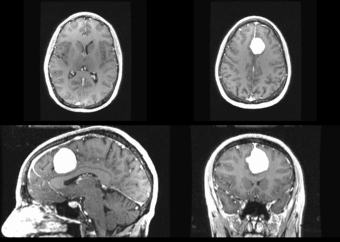

We begin with a tumor growth study. We wish to register the follow up scan to the baseline in order to measure the evolution of the tumor. We perform a rigid registration with six degrees of freedom, three for rotation and three for translation. Our choice of a rigid transformation is driven by our goal of change assessment, we do not want to introduce scaling or non-linear deformation during registration. Data taken from the Registration Case Library.

Left) First scan. Bottom) Follow up scan.

This is an interesting experiment for two reasons. First, tumor change assessment is a common clinical task. As such, there is a need for registration applications to produce high quality results for this type of data. Secondly, the presence of pathology makes registration challenging. If the difference between structures in the two images is considerable, registration algorithms will often produce results of poor quality. This often manifests in poor alignment for rigid registration, or in a large amount of deformation in the area of difference in a non-linear registration.

We further observe different bias fields present in the baseline and follow up images. As a result, we choose a similarity metric that is not sensitive to intensity difference, namely mutual information. We also note that the data dimensions are 128x128x56 for the baseline and 128x128x65 for the follow up. The alignment before registration is shown below.